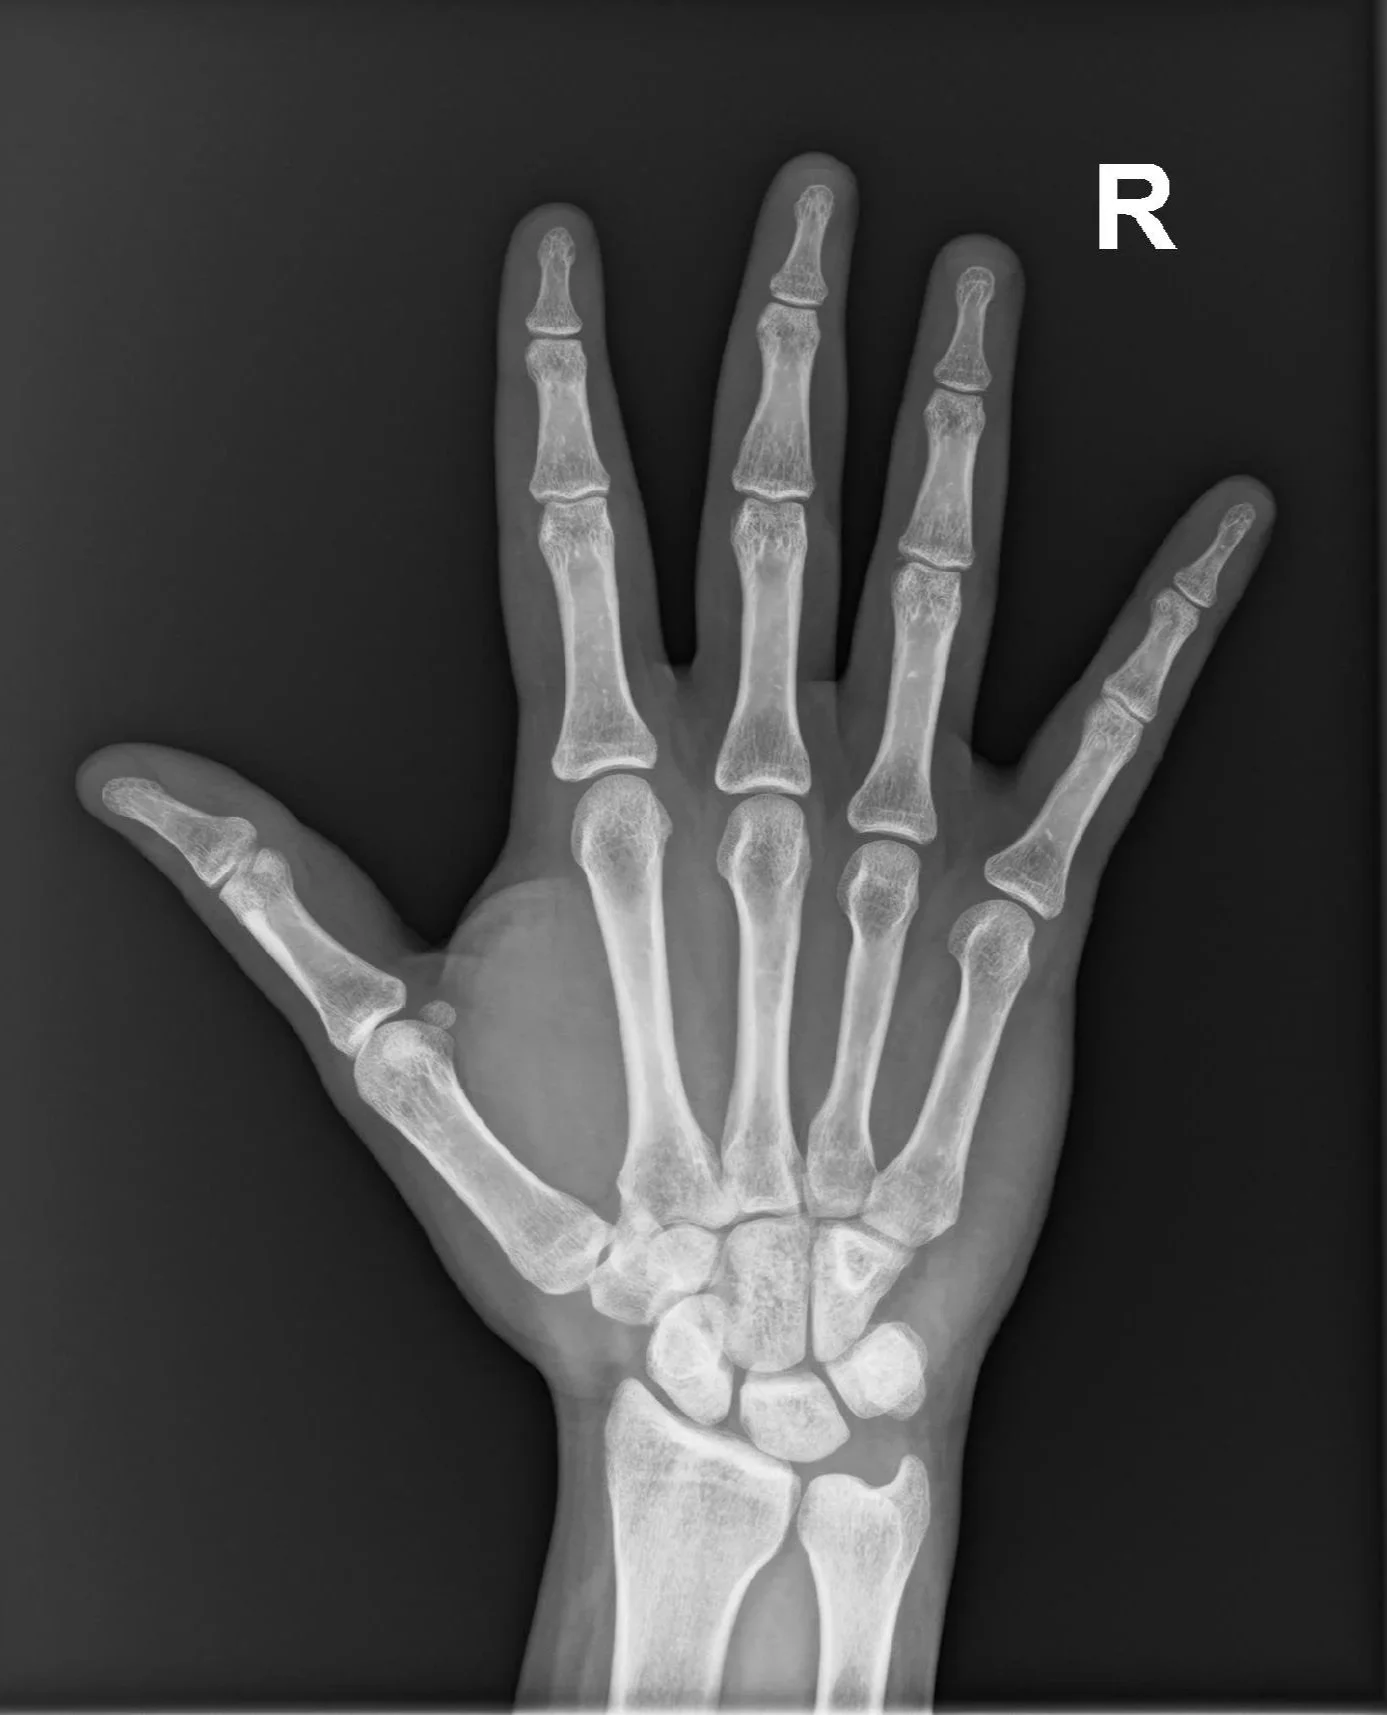

hand x-ray xray radiograph radiology

• An X-ray (radiograph) is a quick, painless imaging test that uses a small amount of x-ray radiation that passes through the body onto a digital detector to form an image. It is particularly useful in assessing bones and lungs.

At Hurstville Radiology, our low-dose digital X-ray uses advanced, dose-efficient technology to produce clear, high-quality images of bones and internal organs with minimal radiation. Designed for your safety and comfort, our modern radiography systems ensure accurate results and trusted care from our experienced radiologists.